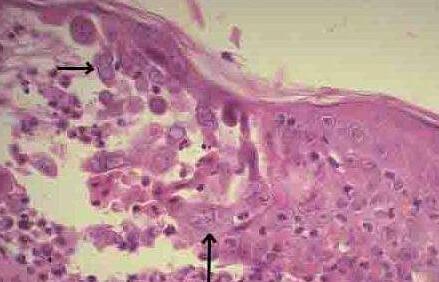

出血 hemorrhage

血液从CAM膜血管内流出血管外,可以表现为血管外出现点状出血或絮状的弥漫性出血等多种形式。

2.5

凝血 coagulation

血管内和血管外蛋白的变性,表现为血管内血流变慢或血栓形成,血管呈现棕黑色,血管外出现混浊和不透明。

2.6

血管融解 blood vessel lysis

CAM膜上小血管壁破裂,小血管融解消失。

鸡胚绒毛尿囊膜试验是一种较早被采用的眼刺激性体外评估方法,绒毛尿囊膜(CAM)是一个呼吸性膜,包围在鸡胚周围。本试验利用孵化的鸡胚中期绒毛尿囊膜血管系统完整、清晰和透明的特点,将一定量受试物直接与鸡胚尿囊膜接触,作用一段时间之后观察绒毛尿囊膜毒性效应指标(如:出血、凝血和血管融解)的变化,这些指标反映血管及血管网的形态结构、颜色和通透性的变化,以及反映绒毛尿囊膜蛋白质变性等现象及其受损程度,然后组合得到一个评分,用于评估受试物的眼刺激性。